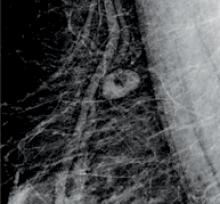

The benefits of computer-aided detection (CAD) for mammography images can be a polarizing topic for many radiologists. The technology has proven to be beneficial in detecting breast calcifications, and today’s CAD software has nearly perfect accuracy in detecting these calcifications. The software has also been noted to help inexperienced radiologists with detecting suspicious areas of breast tissue that may require special attention. However, CAD has not yet proven to be as accurate in its detection of tumors, and for radiologists with a more experienced eye, the software has not made itself as useful. CAD developers are making specific changes to the software that allows for increased visual clarity, context and medical history to make this technology more effective for radiologists across the board.

Just weeks after implementing 3D mammography (breast tomosynthesis) in their practice, radiologists at Weinstein Imaging Associates found breast cancers in three patients that were not seen on the 2D images and the entire staff became instant believers in the new technology.

As a result of routine mammography screening, approximately 1.6 million breast biopsies are performed annually to determine whether a suspicious lesion is malignant or benign. Of these 1.6 million biopsies, approximately 20 percent will result in a positive cancer diagnosis.[1] These numbers are staggering alone, and are just the statistics for one out of more than 200 types of cancers. As radiologists, we strive to provide our patients with the best medical care available, but what we do not always think about is what happens after a sample leaves our office. Errors that occur in the biopsy diagnostic process are specific diagnostic errors that imaging professionals must address.

Advances in digital mammography are evolving as clinicians look to improve breast cancer screening in women. In recent years, new technological trends have emerged; notably, the addition of 3-D breast imaging, or tomosynthesis, which was approved by the U.S. Food and Drug Administration (FDA) in 2011. But as technology improves, questions remain over the recommended frequency of screening for breast cancer.